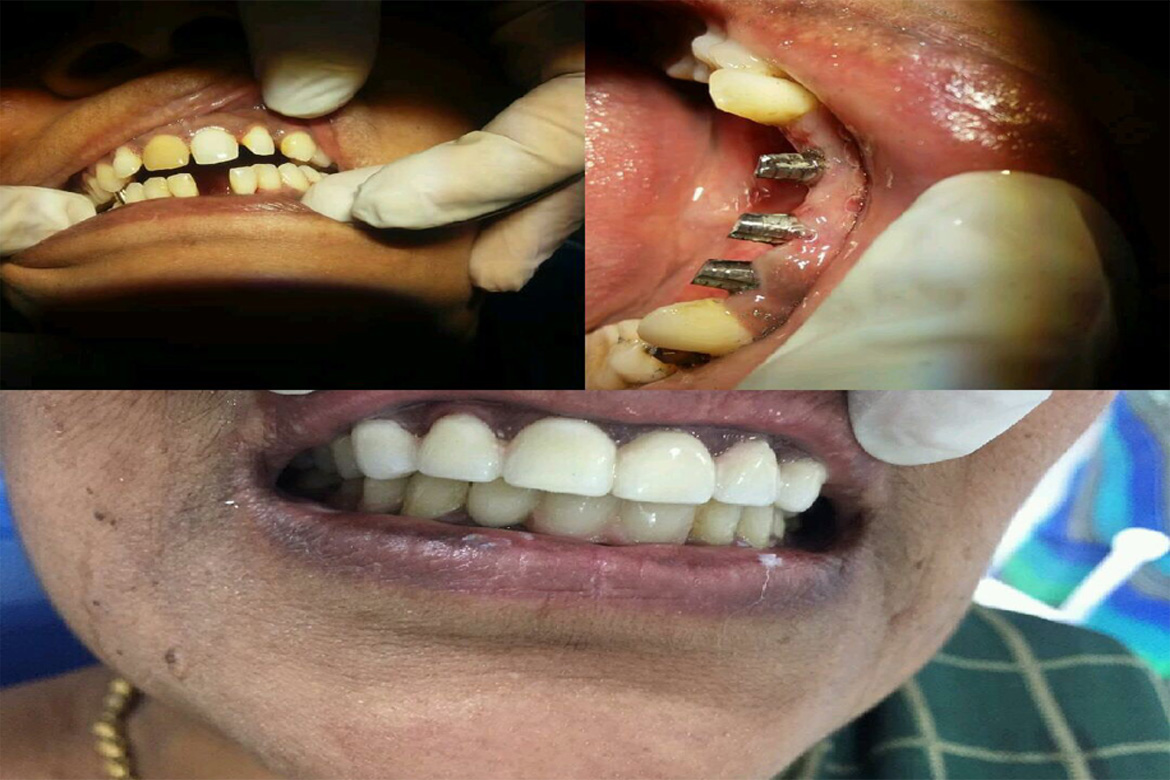

Teeth rehabilitation is very crucial as the loss of teeth will not only have an affect on the choice of food intake but also alters speech and facial contours giving the person an elderly appearance which affects their self confidence.

1 Restores chewing capacity there by improving your over all health

3 Improves your appearance by maintaining bone health and restoring facial contour

4 provides instantaneous fixed results in 3-5 days

5 Revives self confidence

6 Elevates the quality of life